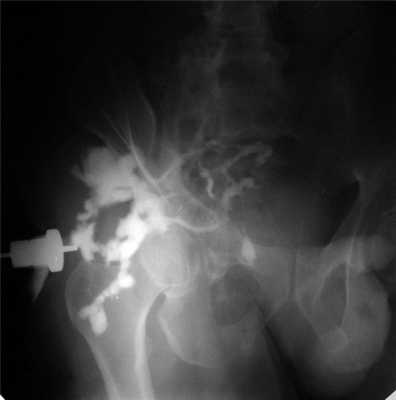

С учетом того, что остеомиелит таза часто сопровождается формированием наружных гнойных свищей, важное место в диагностике отводится фистулографии (рис. 5). Рисунок 5. Фистулограмма больного с остеомиелитом таза: множественные свищевые ходы и гнойные затеки. Использование водорастворимого рентгеноконтрастного вещества позволяет получить полную картину, характеризующую распространение свищевых ходов. Наиболее информативна фистулография в сочетании с КТ.